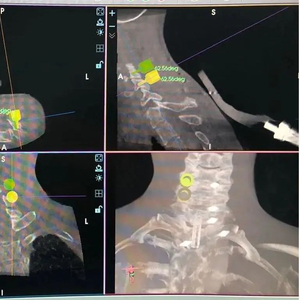

根据规划微创置入颈椎后路侧块螺钉导针

在骨科机器人手术关键技术及配套体系的创建方面,该团队完成了机器人辅助S2AI螺钉、微创颈椎后路侧块螺钉等特定部位的置钉、皮肤表面定位置针(颈、胸、腰)、置针防打滑操作、微创实心椎弓根钉置入、微创小关节融合等关键技术的创新及应用,并研发了相应的工具、装置及软件,对进一步推广骨科手术机器人的临床应用具有重要的意义。